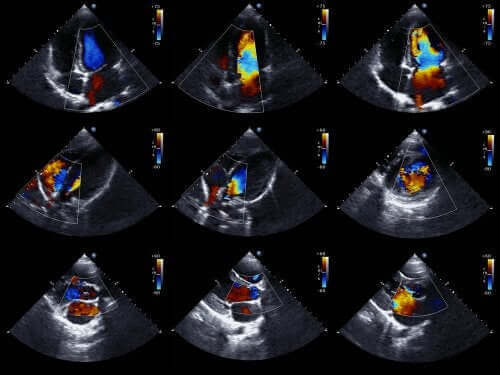

Læger kan normalt diagnosticere denne type afvigelser, før en baby bliver født. For at gøre det bruger de et ekkokardiogram (ultralydsscanning) af fosteret. Dette er en teknik, der bruger lydbølger til at genskabe et bevægeligt hjertebillede.

Takket være dette kan vi se hjertets udseende og undersøge dets funktion, mens en baby stadig er i livmoderen. Med disse oplysninger kan læger programmere behandling umiddelbart efter fødslen.